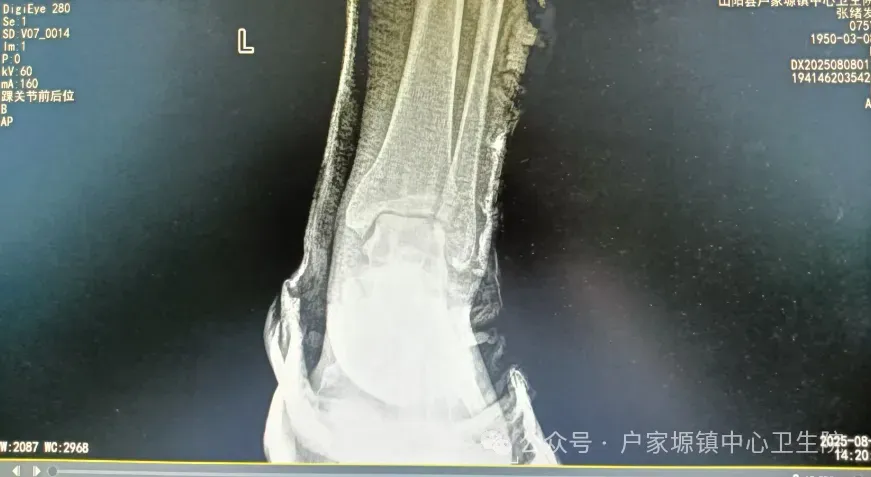

作为服务乡镇群众的“健康守门人”,户家塬镇中心卫生院始终聚焦基层常见骨折病症,组建专业骨科诊疗团队,团队成员均具备多年临床经验,熟练掌握桡骨远端骨折、儿童肱骨髁上骨折、踝关节骨折等常见骨折的手法复位技巧。诊疗中,医生会结合患者年龄、骨折类型、移位情况精准评估,通过“摸、接、端、提、按、摩、推、拿”等传统手法,配合现代影像学检查辅助定位,在避免手术创伤的同时,实现骨折断端的精准复位,最大程度保留关节功能。

此前,一名10岁儿童玩耍时不慎摔倒导致肱骨髁上骨折,家长焦急万分地将孩子送至卫生院。骨科团队迅速响应,仅用20分钟便完成手法复位,随后采用夹板固定保护。复查时,孩子骨折愈合良好,肘关节活动自如。类似的案例在卫生院屡见不鲜——从老年人不慎摔倒导致的手腕骨折,到青壮年劳作时意外造成的脚踝骨折,医生们凭借过硬技术,帮助患者免去手术之苦,缩短恢复周期,减轻经济负担。